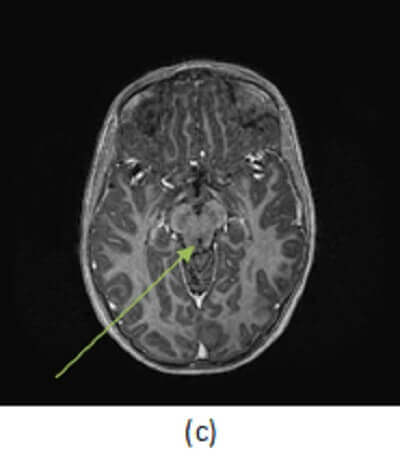

Figure 1: (a,red arrow) FLAIR hyperintense signal expands the right tectal plate with T1 isointense fullness in the same location (b,blue arrow) that does not enchance (c, green arrow).

Tectal plate gliomas are aggressive, infiltrating malignancies of the tectum (the dorsal midbrain). They are generally expansile T2/FLAIR hyperintense minimally enhancing lesions that expand the tectum and compress the midbrain leading to hydrocephalus. They most commonly present as WHO grade 3 (anaplastic astrocytoma) tumors, but may undergo secondary transformation into a glioblastoma multiforme (GBM). Treatment involves resection with adjuvant chemo and radiation therapy but prognosis is poor, with a median survival of 2-3 years.